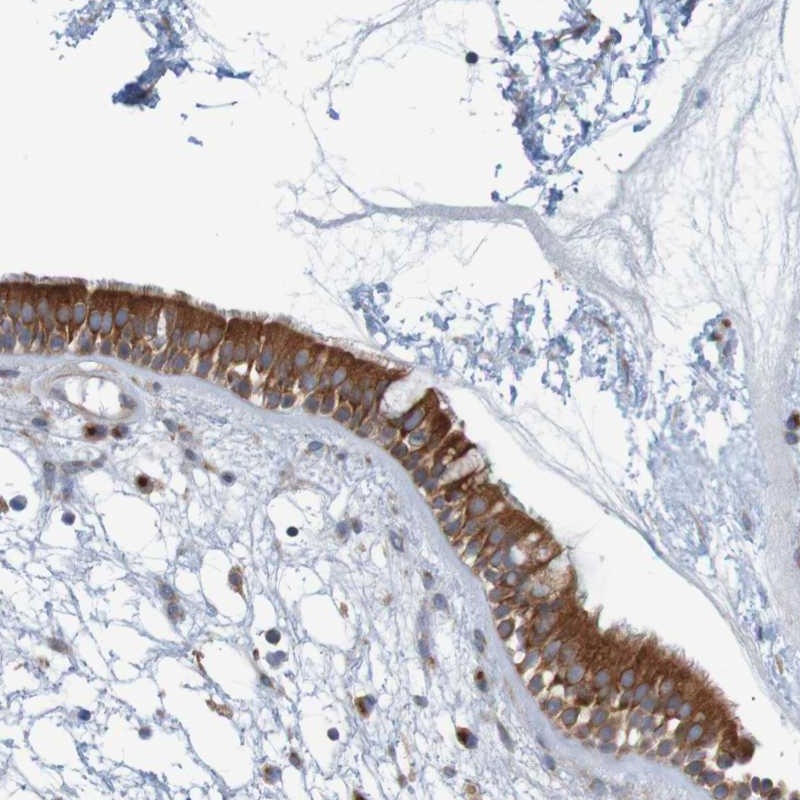

Immunohistochemical staining of human nasopharynx shows strong cytoplasmic positivity in respiratory epithelial cells.